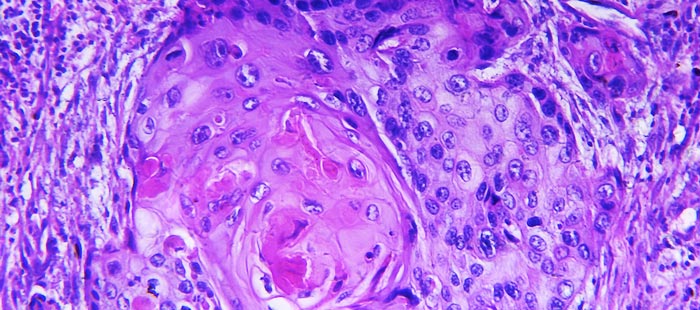

- Плоскоклеточный ороговевающий рак (дифференцированный). Данная патология обуславливается мутацией клетки эпителия, активным ее размножением с появлением клонов, которые накапливают кератин в огромном количестве. Со временем аномальные клетки теряют свои элементы и умирают, откладывая на поверхности новообразования кератиновую массу в виде корочки желтоватого цвета. Высокодифференцированный плоскоклеточный рак характеризуется небыстрым делением патологических клеток, которые нацелены на разрушение сосудов, тканей и костей. Эта разновидность плоскоклеточного рака имеет самые благоприятные прогнозы из всех остальных. Низкодифференцированный плоскоклеточный рак по своему строению напоминает саркому и является более опасным видом заболевания. Аномальные клетки в этом случае имеют веретенообразную форму и размножаются очень быстро, они способны обеспечивать целостность ткани.

Гистологическая классификация

Клетки плоскоклеточного рака могут быть трансформированы в клетки рогового эпителия. Причём тенденция к ороговению разная для разных больных. Гистологически различают ороговевающую и неороговевающую форму плоскоклеточного рака кожи.

Плоскоклеточный ороговевающий рак может быть высокодифференцированным и низкодифференцированным.